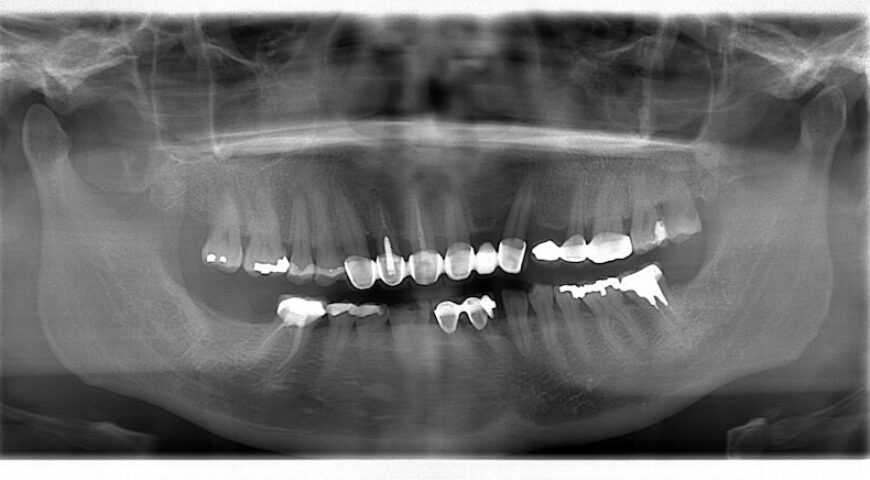

傳統牙周病治療需多次回診,敏感不適也易使患者中途放棄治療。當代牙醫的『一日全口水雷射牙周治療』可減少這些困擾,並於治療後線上關懷,適合疫情時代忙碌或居住各地/國外的患者。葉立維醫師也透過實際案例,帶大家了解牙周病專科醫師採水雷射循序漸進治療牙周病,與患者一起積極保留牙齒的過程。